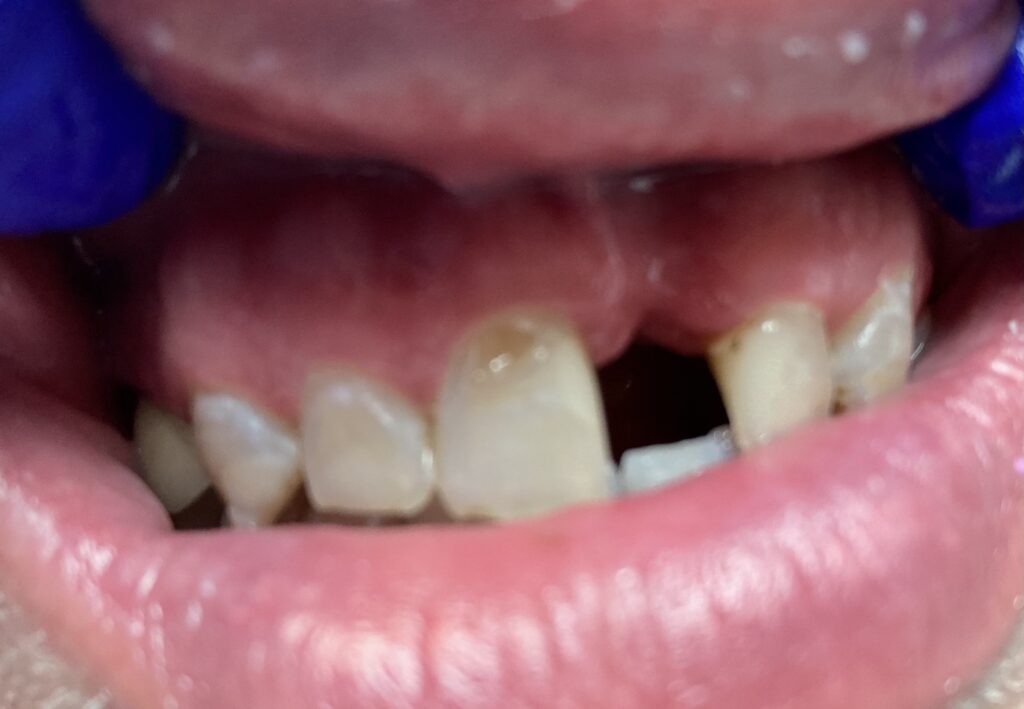

Każdy uśmiech ma swoją historię – my pomagamy ją opowiedzieć na nowo. Dzięki indywidualnie dobranym planom leczenia przywracamy pacjentom nie tylko piękny wygląd zębów, ale również komfort i funkcjonalność w codziennym życiu. Poniżej przedstawiamy wybrane przypadki metamorfoz, które pokazują, jak zaawansowana protetyka, nowoczesne techniki odbudowy oraz precyzyjne leczenie endodontyczne potrafią całkowicie odmienić uśmiech.